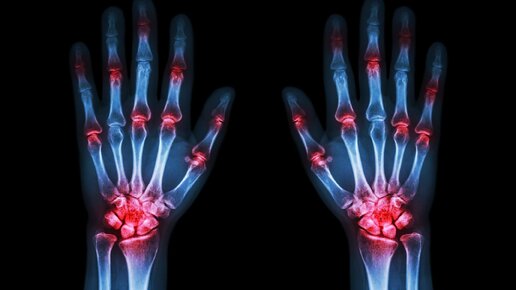

Инфекционное воспаление костей, периостит и миелит — это всё включает в заболевание остеомиелит. Это страшная болезнь, которая несёт за собой пагубные последствия для всех костей человеческого организма.